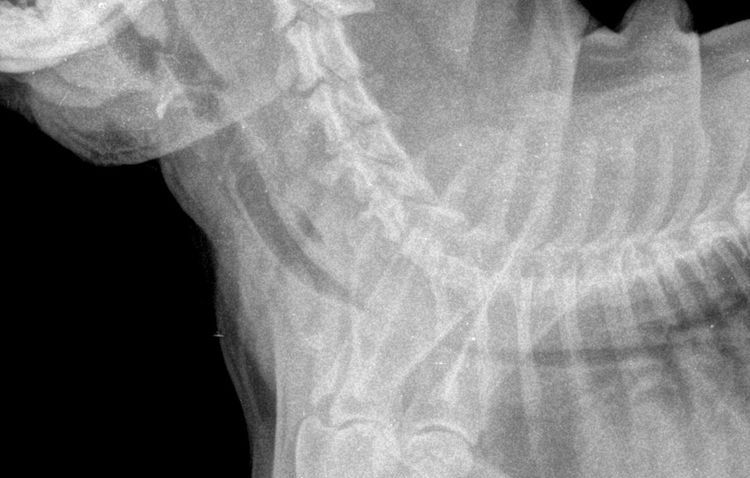

Le diagnostic objectif du collapsus trachéal chez le chien repose sur la radiographie. Si nécessaire, le vétérinaire peut prescrire une trachéoscopie ou une bronchoscopie. Ces interventions sont réalisées sous anesthésie à l'aide d'un dispositif spécial – un endoscope – équipé d'une source lumineuse et d'une caméra photo ou vidéo, qui est inséré dans la trachée pour examiner sa surface interne.

Les résultats des examens instrumentaux permettent de déterminer avec précision les zones de déformation de la trachée et l'importance de la variation du diamètre de sa lumière. Selon le degré d'affaissement de l'anneau trachéal et de rétrécissement de la lumière, on distingue plusieurs stades de sténose :

- Stade 1 - pas plus de 25 % de la lumière est obstruée (une telle sténose est considérée comme compensée et ne nécessite pas toujours de traitement) ;

- Étape 2 - la lumière de la trachée est rétrécie de 50 % ;

- Stade 3 - 75 % de la lumière est bloquée par une membrane affaissée ;

- Stade 4 - la trachée est complètement fermée.